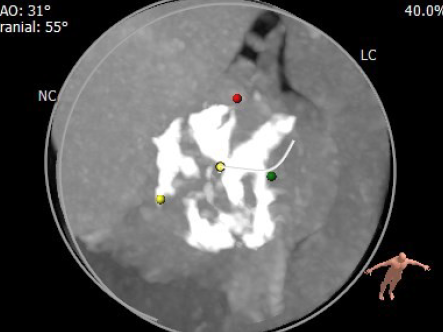

图4. Circle Method方法评估瓣膜尺寸,释放位置和风险程度

2. 考虑到患者二叶式主动脉瓣 Type1型,主动脉根部极重度的钙化,以及R-L融合钙化脊往下垂坠的尖锐钙化赘生物,CT明显可见左窦瓣叶几乎无法活动形成Lazy Leaflet结构,选择植入爱德华的SAPIEN 3经导管主动脉瓣膜能使患者获益最大,因为其瓣架是钴铬合金,具有很强的支撑力,能推开钙化保持正圆形的瓣架,使术后有更好的血流动力。但也正因为如此,需要在术前术中进行最精细的评估,确保强力推开钙化同时避免瓣环破裂风险。因此一方面术前CT精准评估瓣环大小,综合考虑downsize选择瓣膜尺寸;另一方面,术中通过球囊预扩,将极重度钙化瓣叶扩开,评估推开程度,便于后续的瓣膜跨瓣及释放操作。